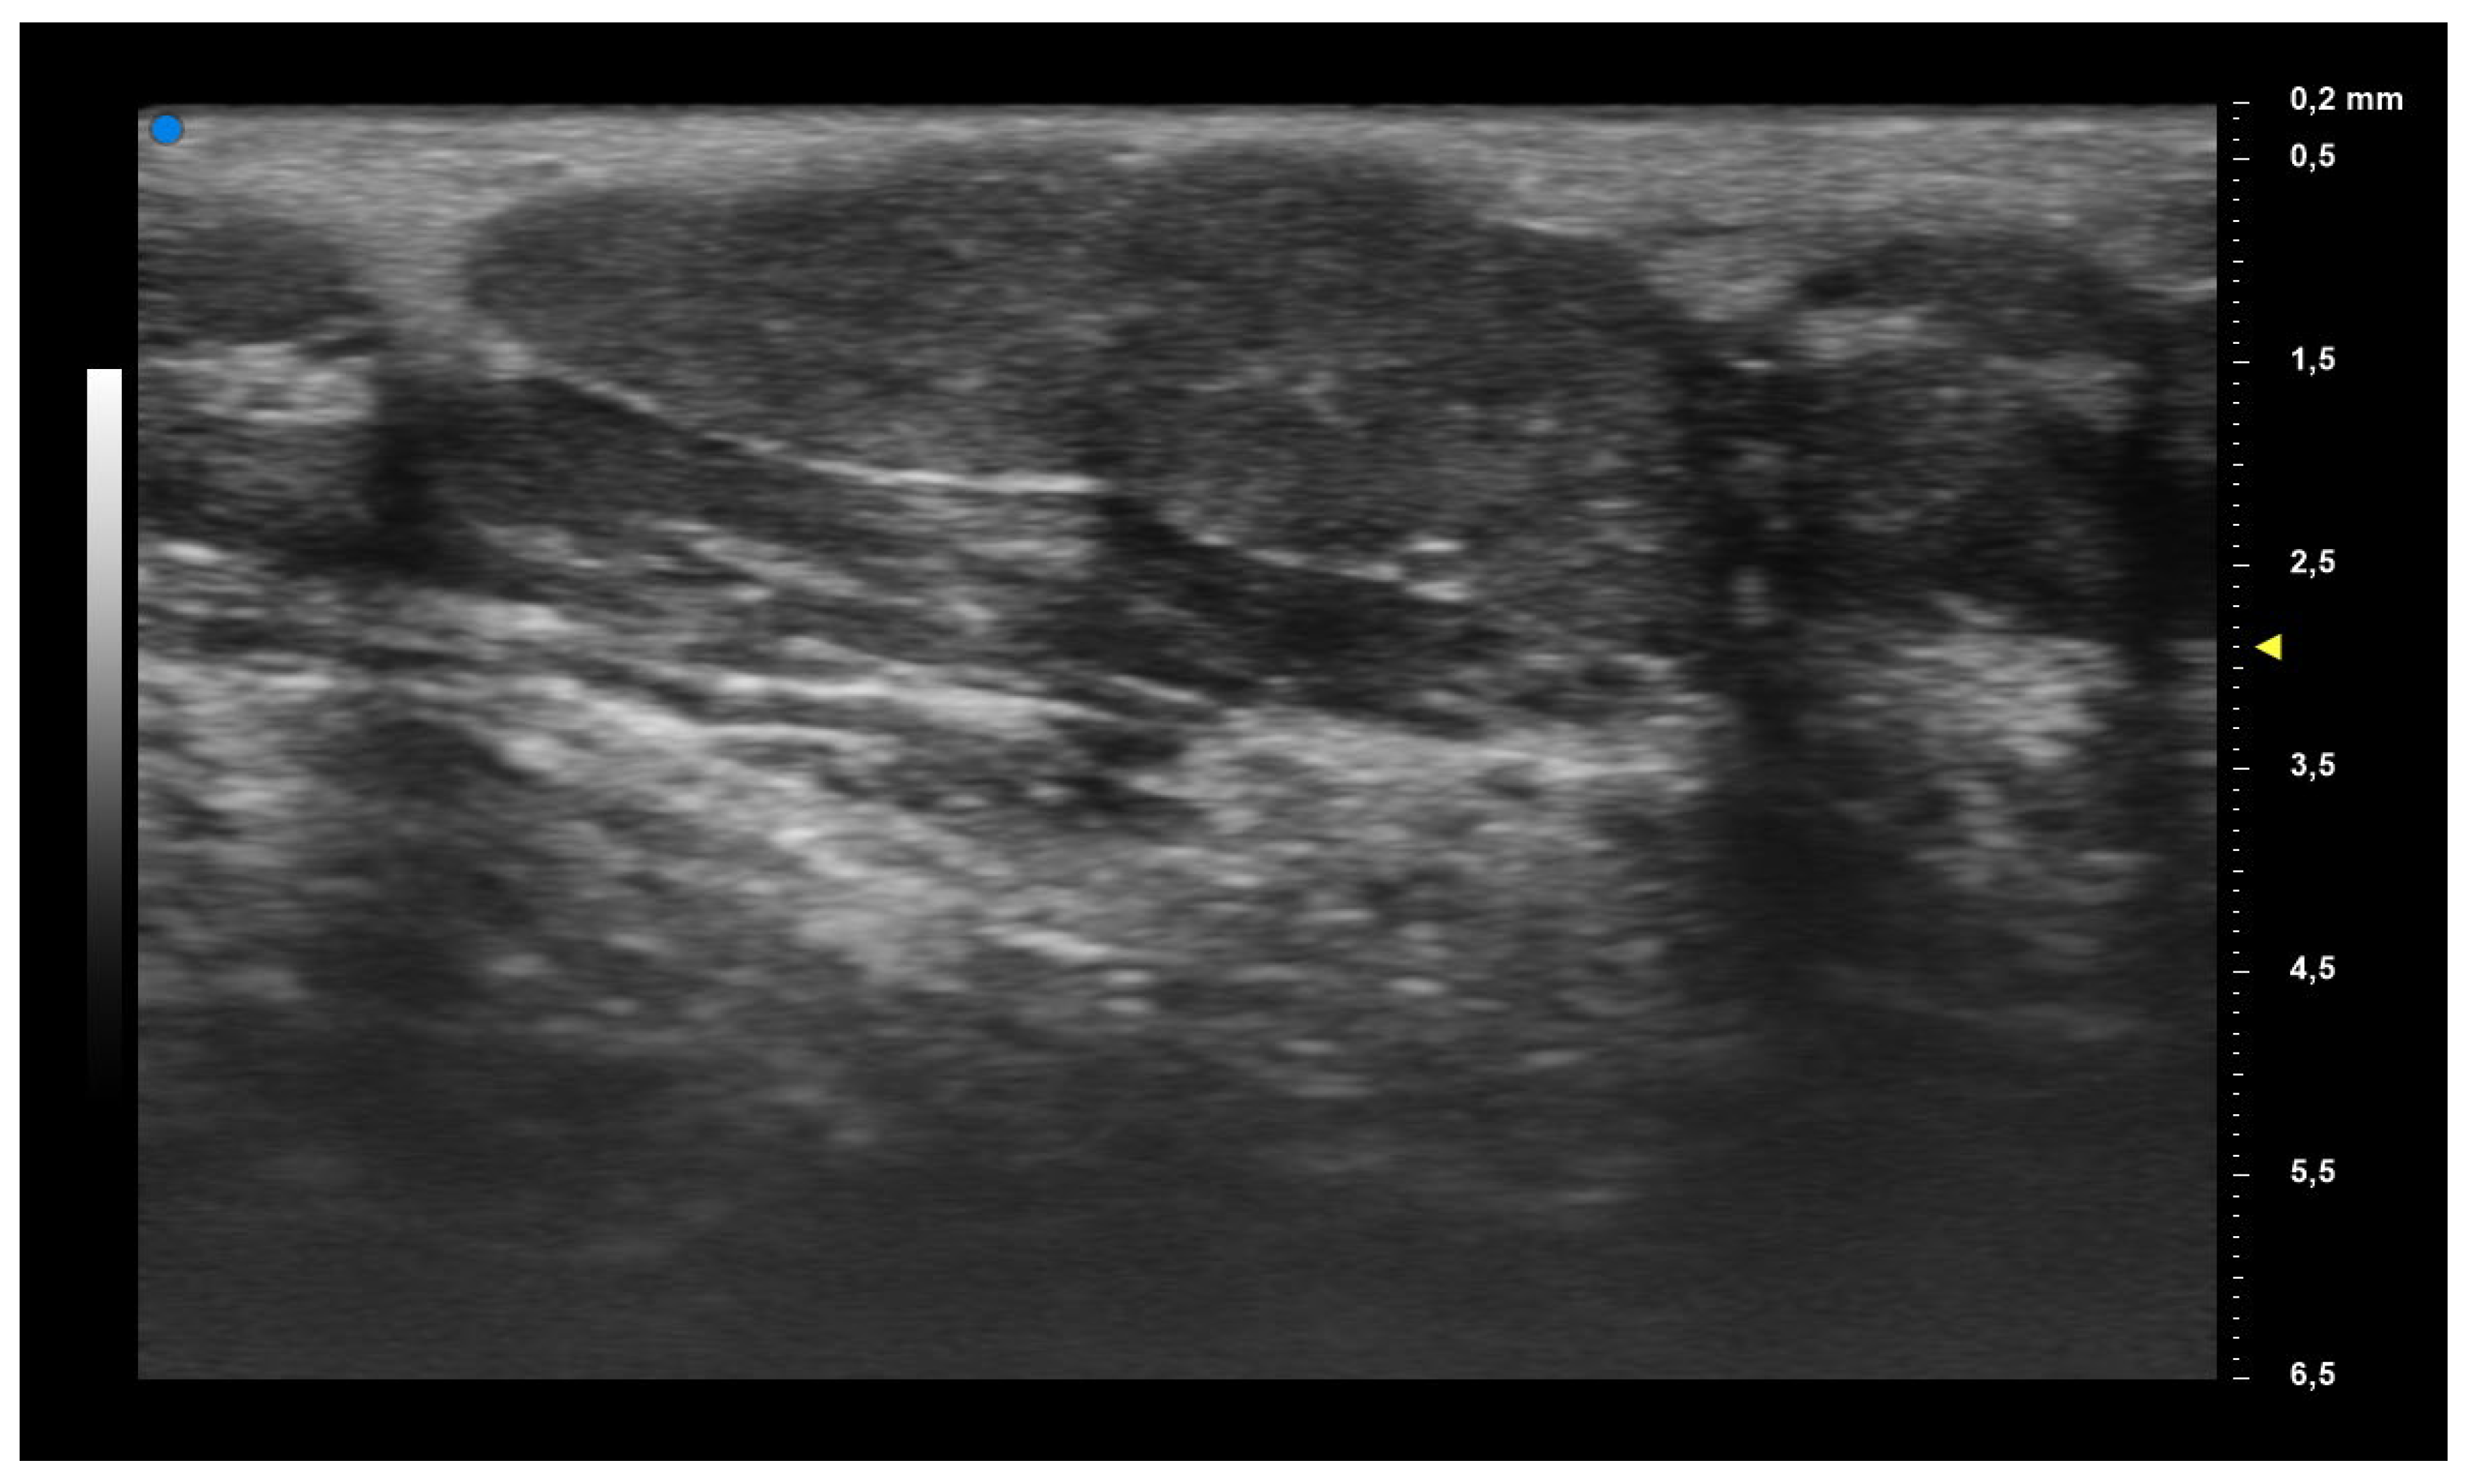

| UHFUS Characteristics | Sicca Syndrome (n = 4) | Parotitis (n = 2) | Non-Sicca, Non- Parotitis (n = 6) | Total (n = 12) |

|---|---|---|---|---|

| Grade 1 | 3 (75%) | 1 (50%) | 4 (67%) | 8 (67%) |

| Grade 2 | 0 (0%) | 1 (50%) | 1 (17%) | 2 (17%) |

| Grade 3 | 1 (25%) | 0 (0%) | 1 (17%) | 2 (17%) |

| Mild vascularization | 1 (25%) | 1 (50%) | 1 (17%) | 3 (25%) |

| Moderate vascularization | 3 (75%) | 1 (50%) | 5 (83%) | 9 (75%) |